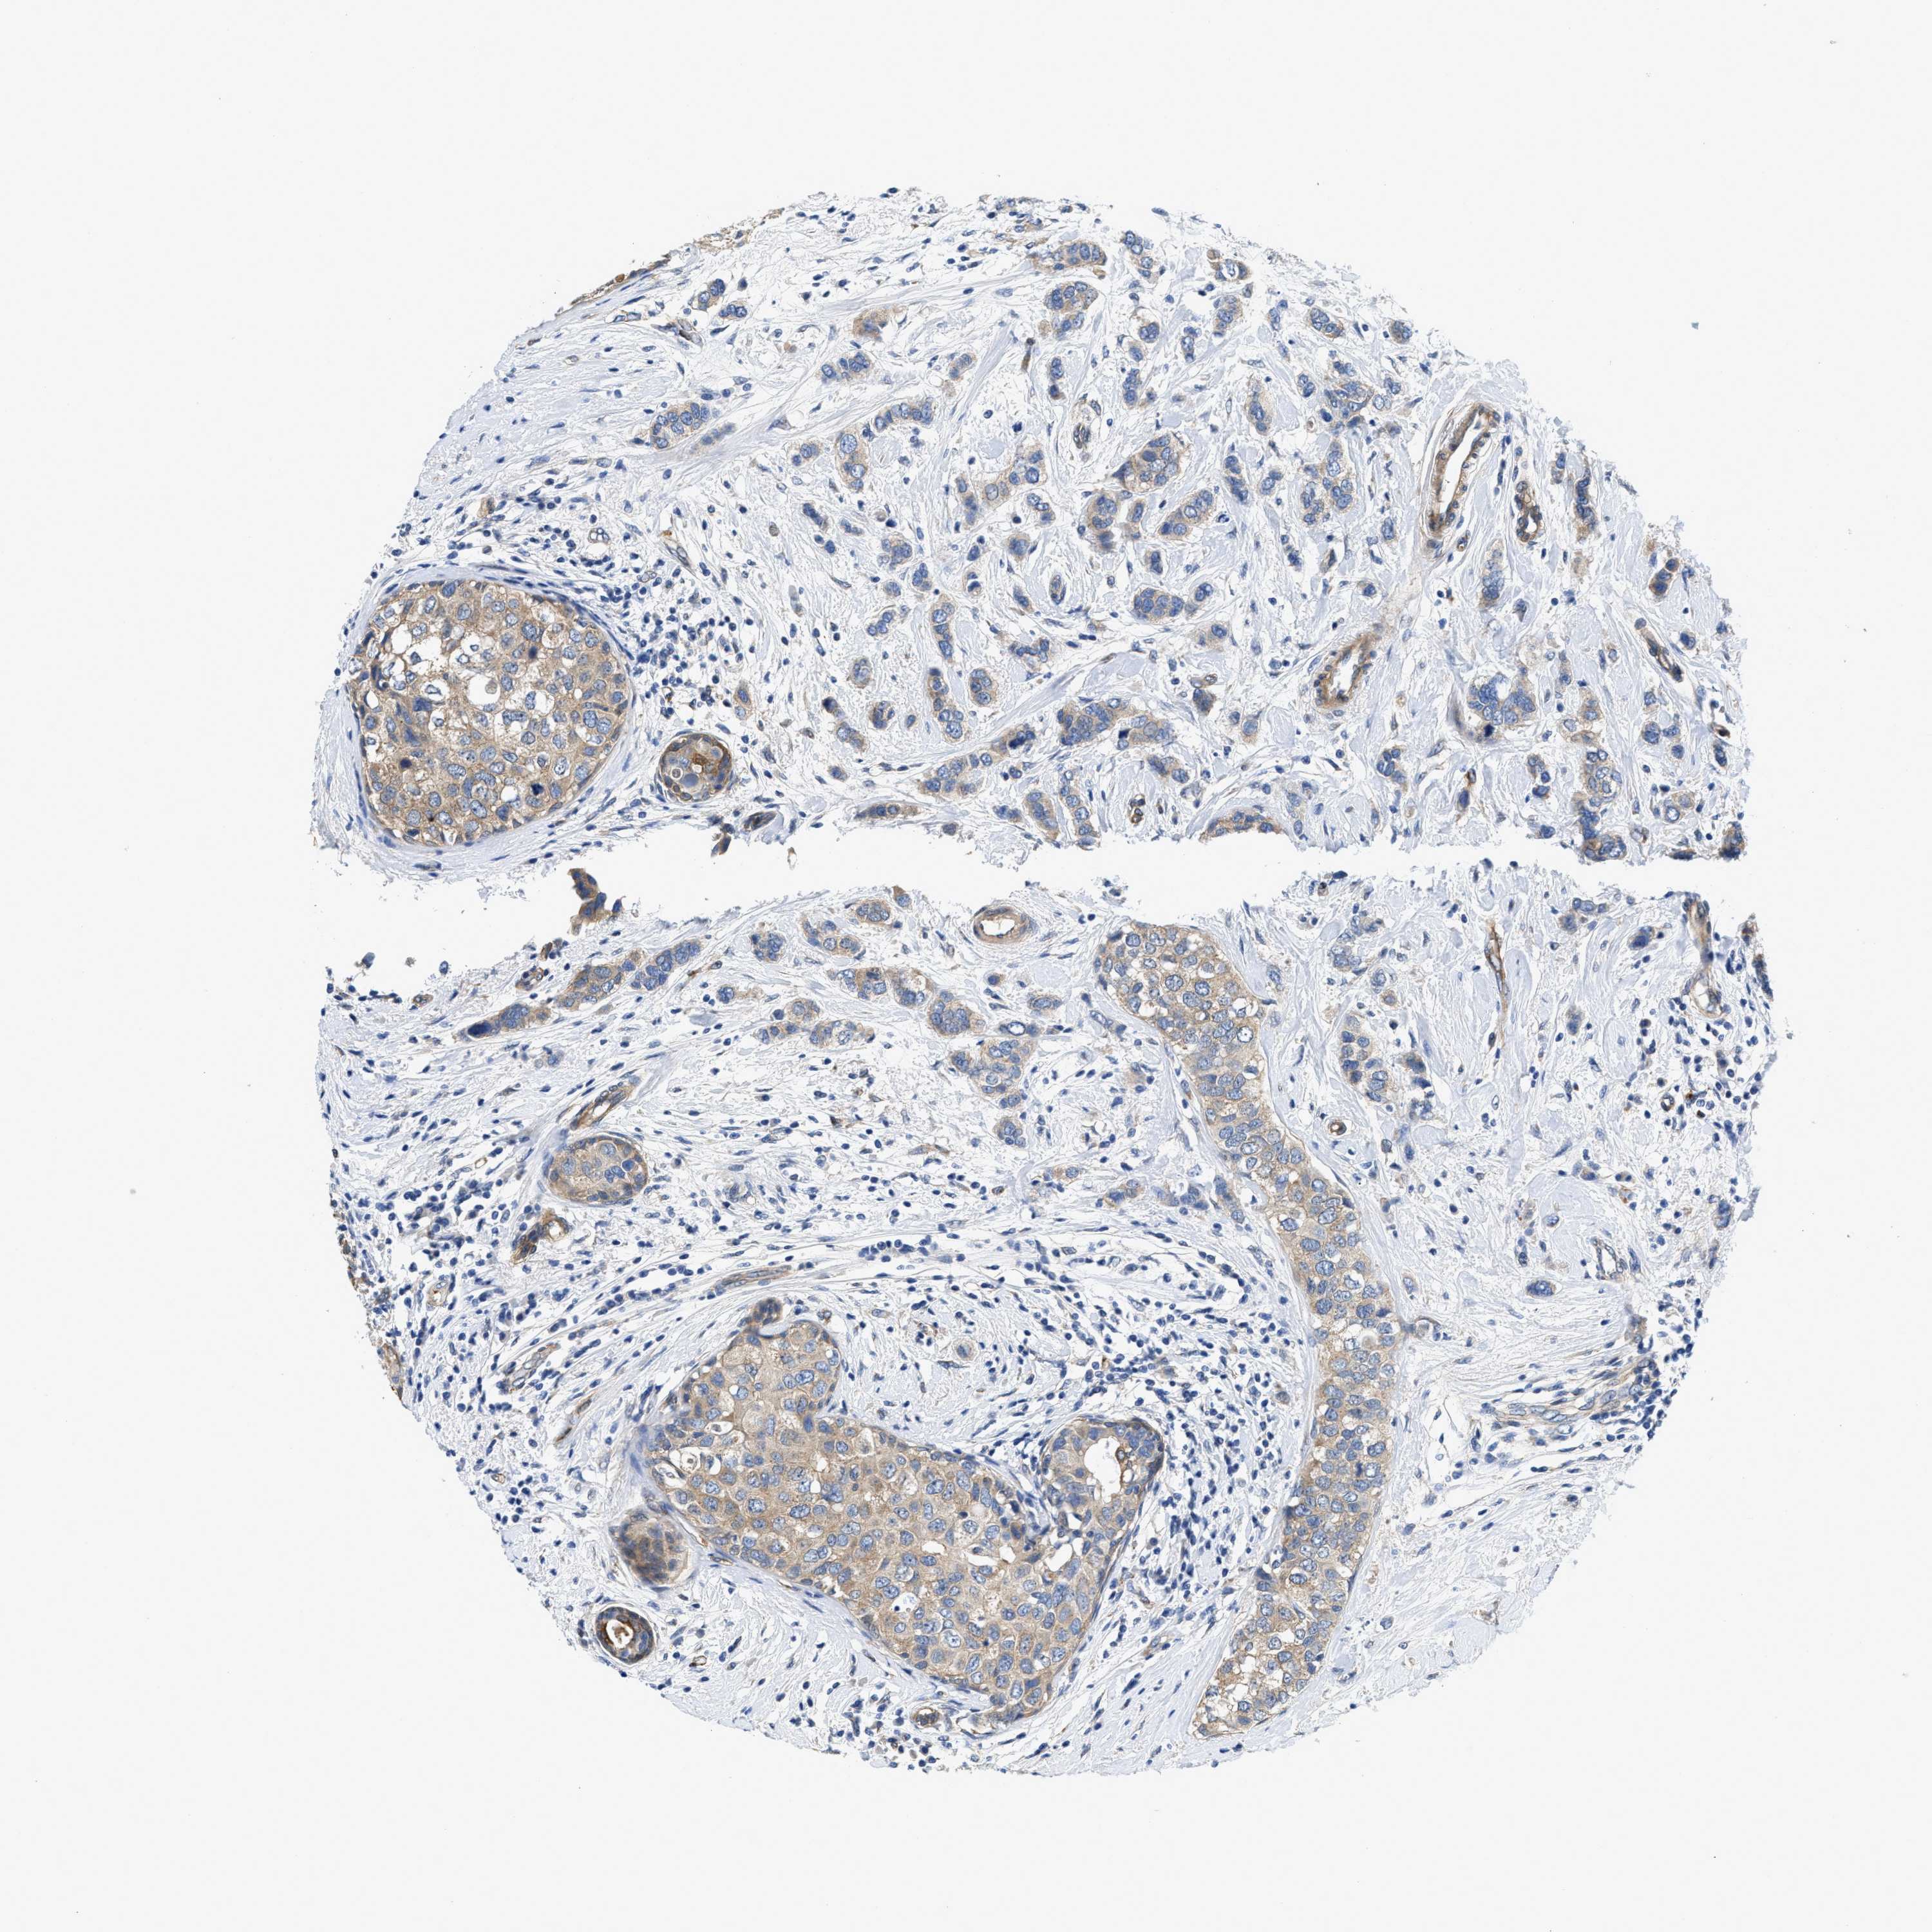

BRCA TCGA BRCA VALIDATION PROTEIN EXPRESSION

ANTIBODIES

AND

VALIDATION